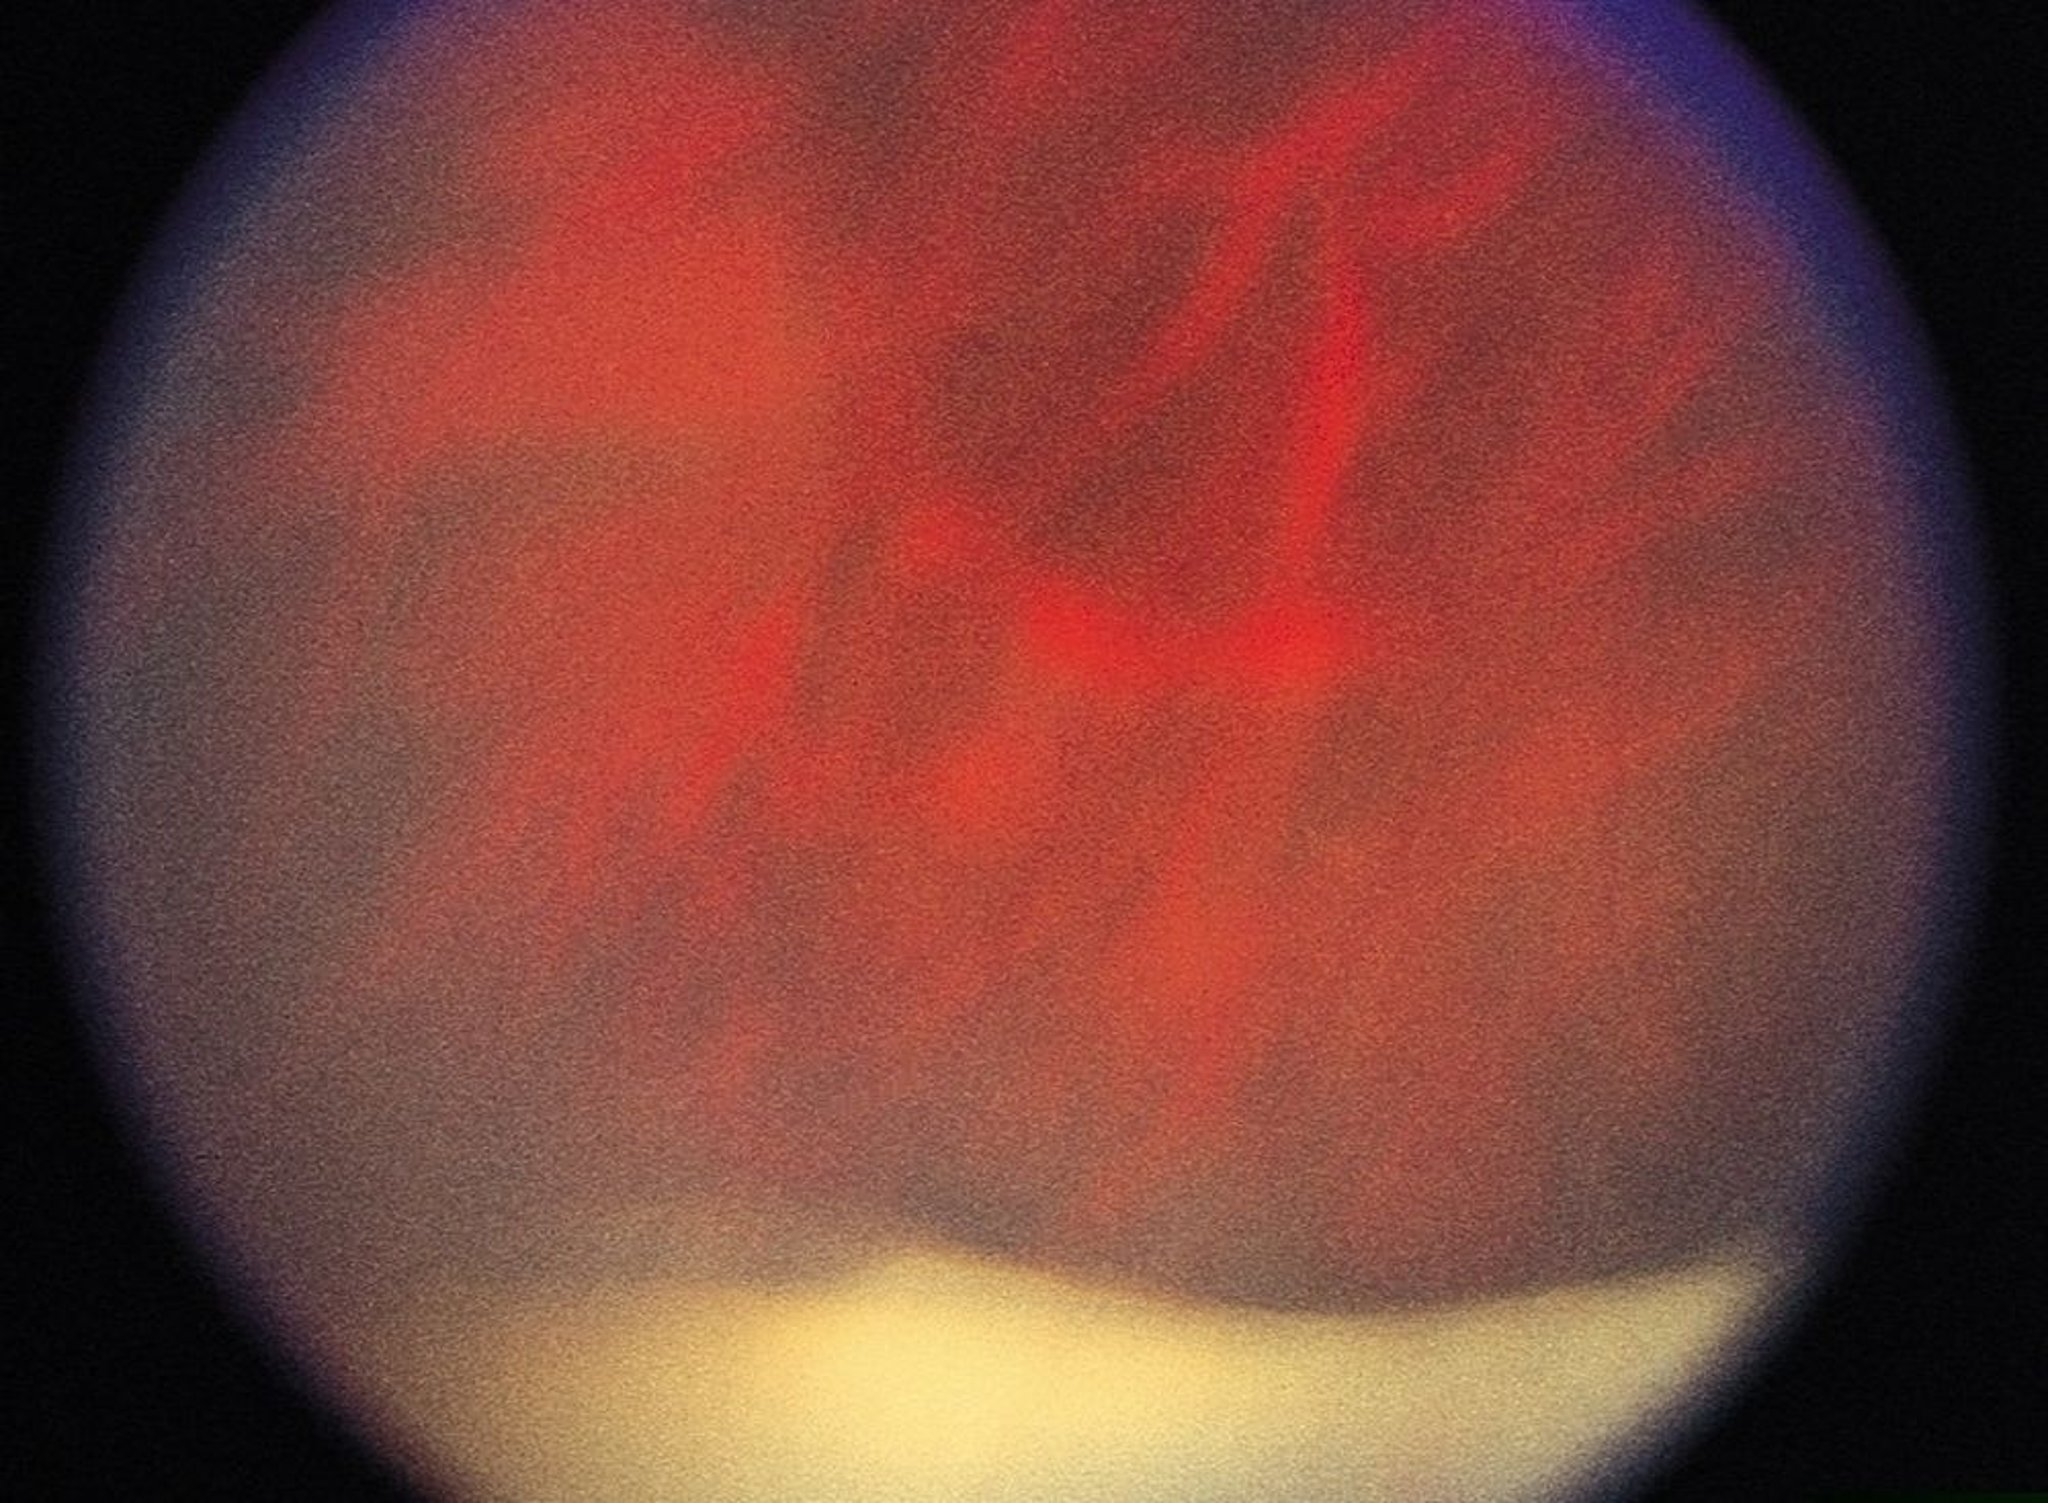

Viêm màng bồ đào (trung gian)

Trong viêm màng bồ đào trung gian, tập hợp các tế bào viêm có thể ngưng tụ trên mặt phẳng phân tích và trông giống như những quả bóng tuyết; Sự hợp lưu của cái gọi là quả cầu tuyết gây ra hình dạng bờ tuyết cổ điển, có thể nhìn thấy (trong hình ảnh này, lớp lót màu trắng ở dưới cùng) bằng kính soi đáy mắt gián tiếp.